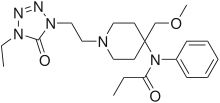

Anilidopiperidines